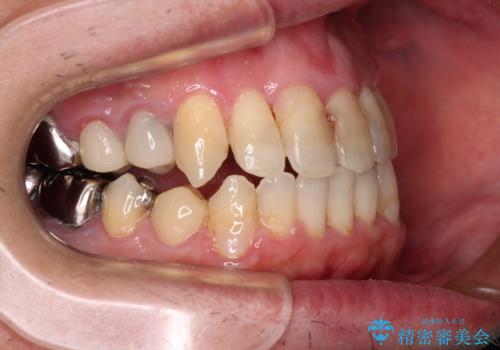

- 飛び出している上顎前歯と、奥歯に多くある銀歯を気にして来院された患者様です。

マウスピースで矯正を行いたい反面、一旦早めに前歯を整えたいというご希望があったため、まずは上顎前歯をワイヤー装置で整え、その後インビザラインにて仕上げていくこととしました。

ワイヤー矯正を併用したことで、上顎前歯はあっという間に整いました。